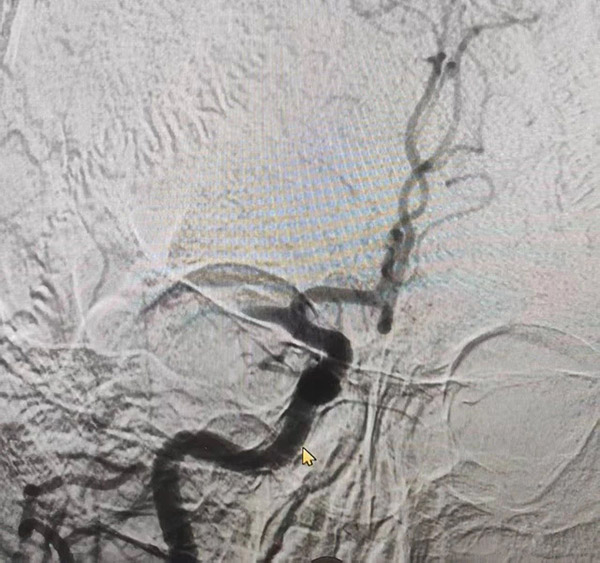

8点整,手术正式开始。景雪峰主任手持导丝导管经股动脉,在直径仅2毫米的脑血管中“穿针引线”。“注意!血管迂曲段接近血管瘤,动作轻柔避免骚扰血管瘤!”导管室内,心电监护仪滴答作响,所有人的目光紧盯着血管造影屏幕——堵塞部位像一团“淤泥”死死堵住大脑中动脉,而旁边鼓起的血管瘤如同“不定时炸弹”,稍有不慎就可能引发颅内出血。

术前大脑中动脉血栓

术后血管通畅

8点40分,取栓导管精准抵达病变部位;8点45分,血栓捕获,抽吸……一系列动作行云流水。8点59分,当黑色血栓被完整抽出的瞬间,屏幕上停滞的血流突然“流动”起来,手术室里响起压抑的欢呼声。“第三次血栓,又是高龄患者,血管条件差到极致,但我们必须赢,因为背后是一个家庭的希望。”景雪峰主任术后坦言。